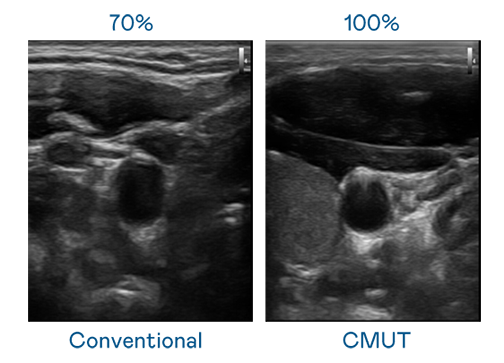

CMUT 技术是一种用电容式微机电元件来产生超音波讯号的技术。与传统 PZT 压电式技术相比,CMUT 频宽增加 30%,更宽频的超音波讯号让影像解析度大幅提升,是实现高影像品质医疗超音波扫描、促进精准医疗发展的关键技术。

大频宽带来超清晰影像

超音波影像的解析度高低,首先取决于探头能发出的讯号频宽。恒峰国际 CMUT 可提供高清晰的超音波讯号,提供高频宽、高灵敏度、影像纹理细节更高的超音波影像,协助医护人员缩短影像判读时间及利用精准的医疗影像进行诊断。